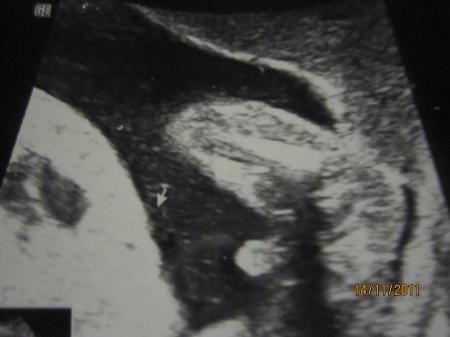

Nr. 3 da sieht man ihn, den Schniebel